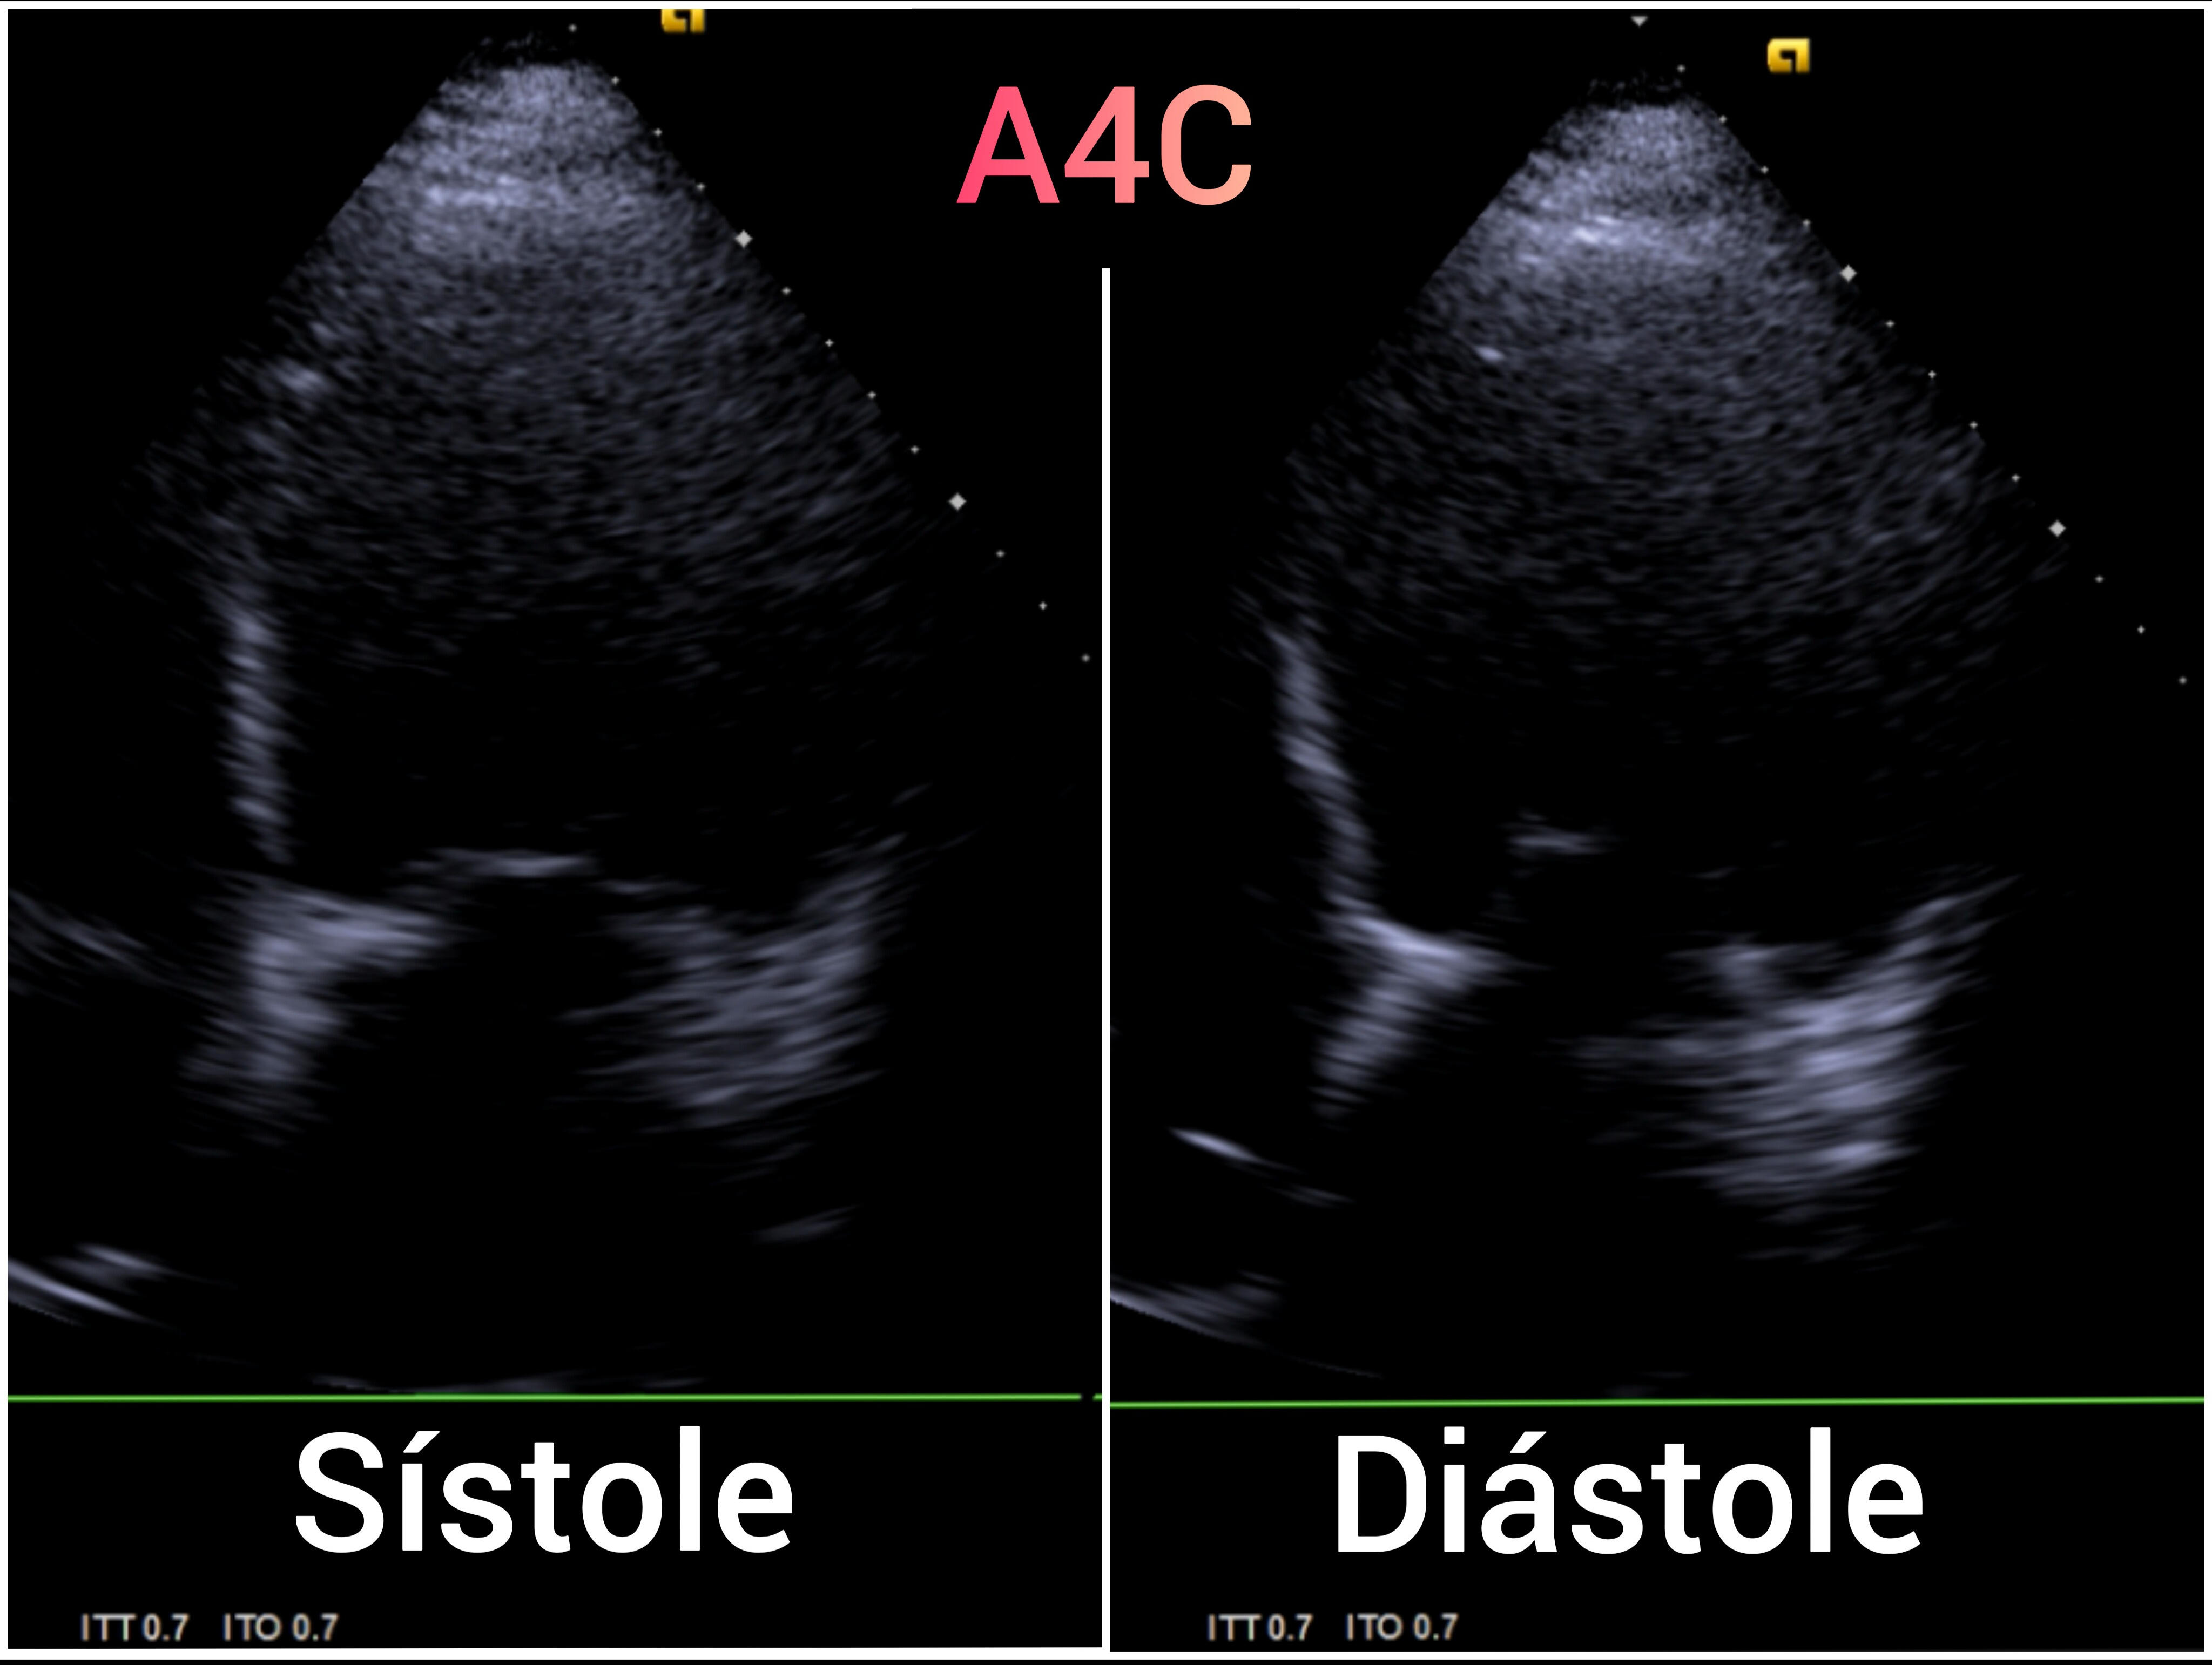

EcoCardioscopia: Mejoría de contractilidad subjetivamente respecto a previo, cavidades izquierdas dilatatadas tanto VI como AI.